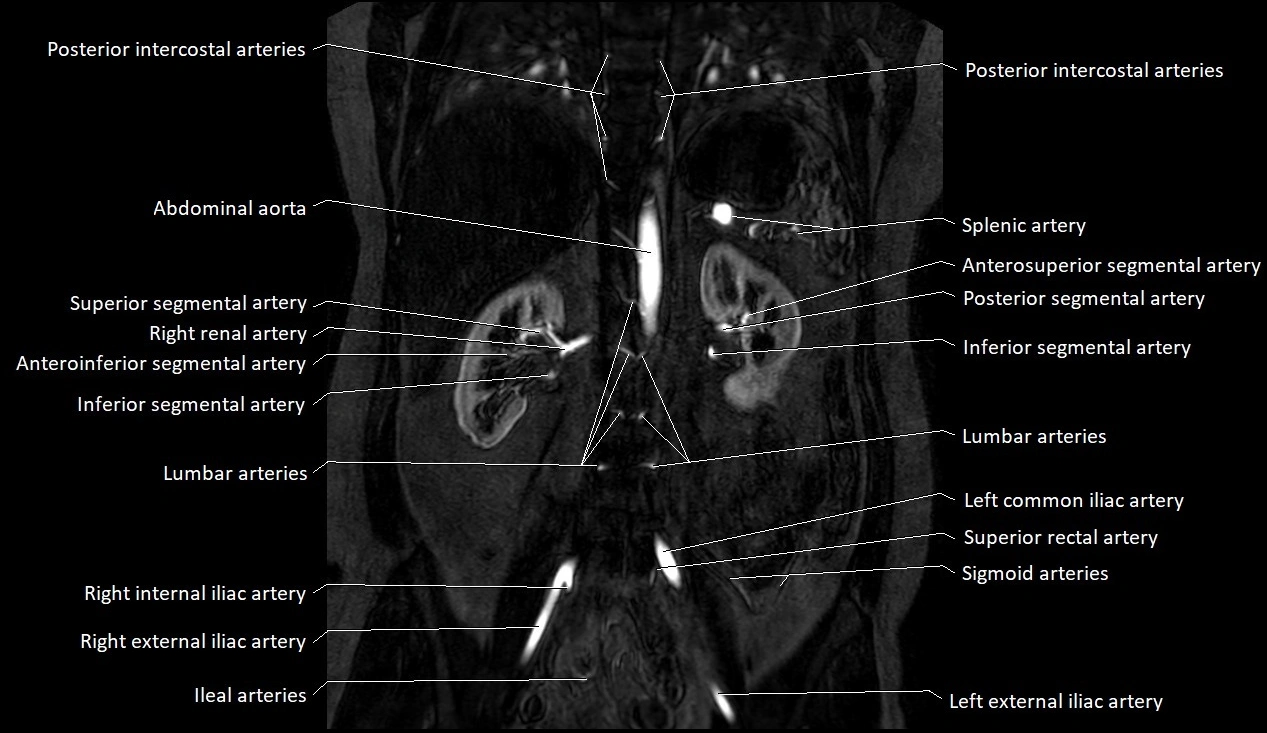

MRA (Magnetic Resonance Angiography):

• Contrast-enhanced MRA provides high-resolution imaging of the aorta and its branches

• Allows 3D reconstruction of visceral, parietal, and terminal branches

• Excellent for evaluating aneurysm size, dissection flap, stenosis, or preoperative planning

• Non-invasive alternative to conventional angiography

MRI images

image